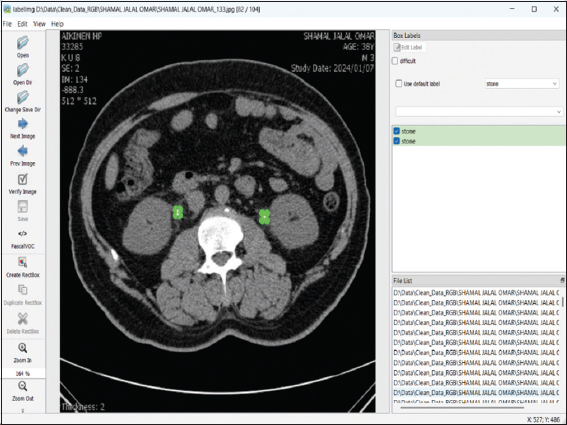

A specialized open-source Python application was utilized for annotating medical CT scans. The labeling process was executed through labelImg.py, a commonly employed annotation tool incorporated within the Anaconda environment. CT scans illustrating nephropathy (Fig. 2) and kidney stones (Fig. 3) were meticulously examined and documented under the direct supervision of a qualified nephrologist to guarantee clinical precision. Every image was carefully annotated, and the labels were stored in three distinct formats: JavaScript Object Notation (JSON), TXT, and Extensible Markup Language (XML). For the purpose of creating precise segmentation masks unique to each annotated image, the chosen formats were meant to improve compatibility with later processes. In medical image analysis, the manual way ensured better annotations, which are necessary for supervised learning models to work.

thumblarge

Fig. 3. Labelling a kidney stone.